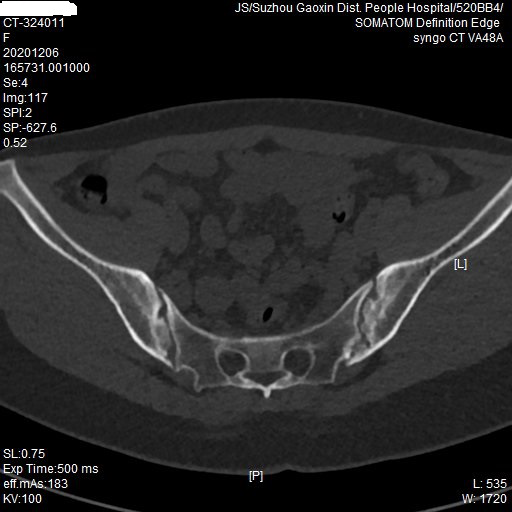

日前,被腰背部疼痛折磨了两年的22岁的小伙子任先生,来到我院风湿免疫科就诊,自诉经常腰背部疼痛,时常夜间痛到无法入眠。为解决这个腰背部疼痛,他说自己可谓是历经艰辛,曾外院查腰椎核磁,提示腰椎间盘突出,并进行了手术治疗。万万没想到是,虽然手术做完了,腰背部疼痛并没有得到缓解。小伙子非常苦闷:一个小小的腰背痛,到底是一种什么疑难杂症呢?经朋友推荐,于是来到专治疑难杂症的风湿免疫科就诊。卫荣教授详细询问病史及查体后,告诉这位小伙子:“这可不是什么疑难杂症,是风湿免疫科的常见病。”对其完善了HLA-B27和骶髂关节CT等检查后,最终确诊为强直性脊柱炎。经积极治疗后,小伙子目前腰背部疼痛基本缓解。他激动地说:“现在终于能畅快地伸伸懒腰,可以一觉睡到大天亮了。”

卫教授介绍,强直性脊柱炎别称“竹竿病”,因为其发病一般先侵犯骶髂关节,然后沿脊柱逐渐向上发展累及脊椎,严重时侵犯到腰椎、胸椎甚至颈椎,致使脊背僵硬如弓——不能弯背、仰头和旋转,髋关节强直——不能下蹲和抬腿,被老百姓称为“竹竿病”。国内最新研究报道,强直性脊柱炎患者的诊断平均延误5-10年,往往会被腰椎间盘突出或者腰肌劳损遮盖掉真实的病情。所以,及早诊治尤其重要,这需要患者及时就诊及医生的“火眼金睛”。